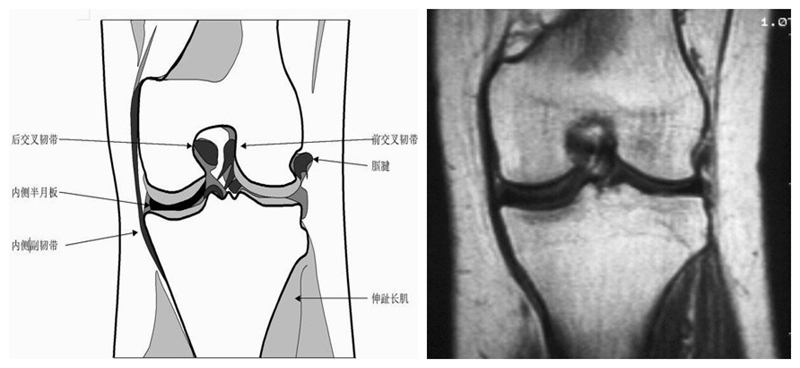

膝关节冠状面MRI解剖

显示内外侧副韧带、腘肌和拱状韧带,有无信号和结构改变,侧重关节胫股软骨的两边和半月板的体部。

冠状位解剖第四层